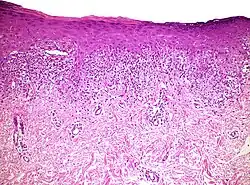

| Histopathology of lichenoid drug reaction. It resembles lichen planus because of irregular epithelial hyperplasia, focal hypergranulosis, orthokeratosis, and a “saw-tooth” pattern of rete ridges. | |